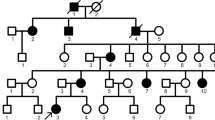

Thirty-one individuals of a Korean family, 9 of whom were affected and 22 unaffected by amelogenesis imperfecta, were enrolled. Whole-exome sequencing was performed on 12 saliva samples, including samples from 8 affected and 4 unaffected individuals. The possible candidate genes associated with the disease were screened by segregation analysis and variant filtering. In silico mutation impact analysis was then performed on the filtered variants based on sequence conservation and protein structure.

A family comprising 31 members across four generations was enrolled in this study. Of the 31 members, 9 were affected, and 22 were unaffected. Written consents were obtained for using the clinical medical information from 12 individuals of the family, including 8 subjects affected by AI. Since four of the participants were minors, written consent was obtained from their guardians. Saliva samples were collected to extract DNA. We analysed the family members affected by AI who gave their informed consent; these participants had no specific disease or clinical history besides amelogenesis imperfecta. This clinical research was approved by the Institutional Review Board of Yonsei University College of Dentistry (Yonsei IRB No. 2-2018-0055, Approved on 28 January 2019). This clinical study was conducted in accordance with the Helsinki Declaration.

A total of 12 samples were used for WES analysis, consisting of samples from 7 females and 5 males, 8 of which were AI patients. All patients had permanent dentition, except for a 9-year-old patient (Fig. 1; individual 4-8) with mixed dentition.

WES was performed on all the consenting individuals of the family. The AI patients from the family showed two possible inheritance patterns: autosomal dominant and X-linked dominant. A total of 20 variants were identified through segregation analysis: 14 variants were accounted for by autosomal dominant inheritance, and 6 variants are explained by X-linked dominant inheritance (Table 3 and Supplement Table 3). Four of the 20 variants met all the filtering criteria (Table 1). Three missense variants in these three genes are rare in the Asian population: rs143029488 in MROH7 with Asian MAF of 0.0105, rs7718054 in FAT2 with Asian MAF of 0.0437, and rs191165757 in HCCS with Asian MAF of 0.0017. A missense variant (ENST00000240050; c.92C>G) in MTERF2 had an undefined MAF (Table 3). For example, the variant in HCCS showed a heterozygous genotype in the affected family member 2-2, but was not present in the unaffected family member 3-6 (Table 4). All 4 variants were used in the subsequent mutation impact analysis.